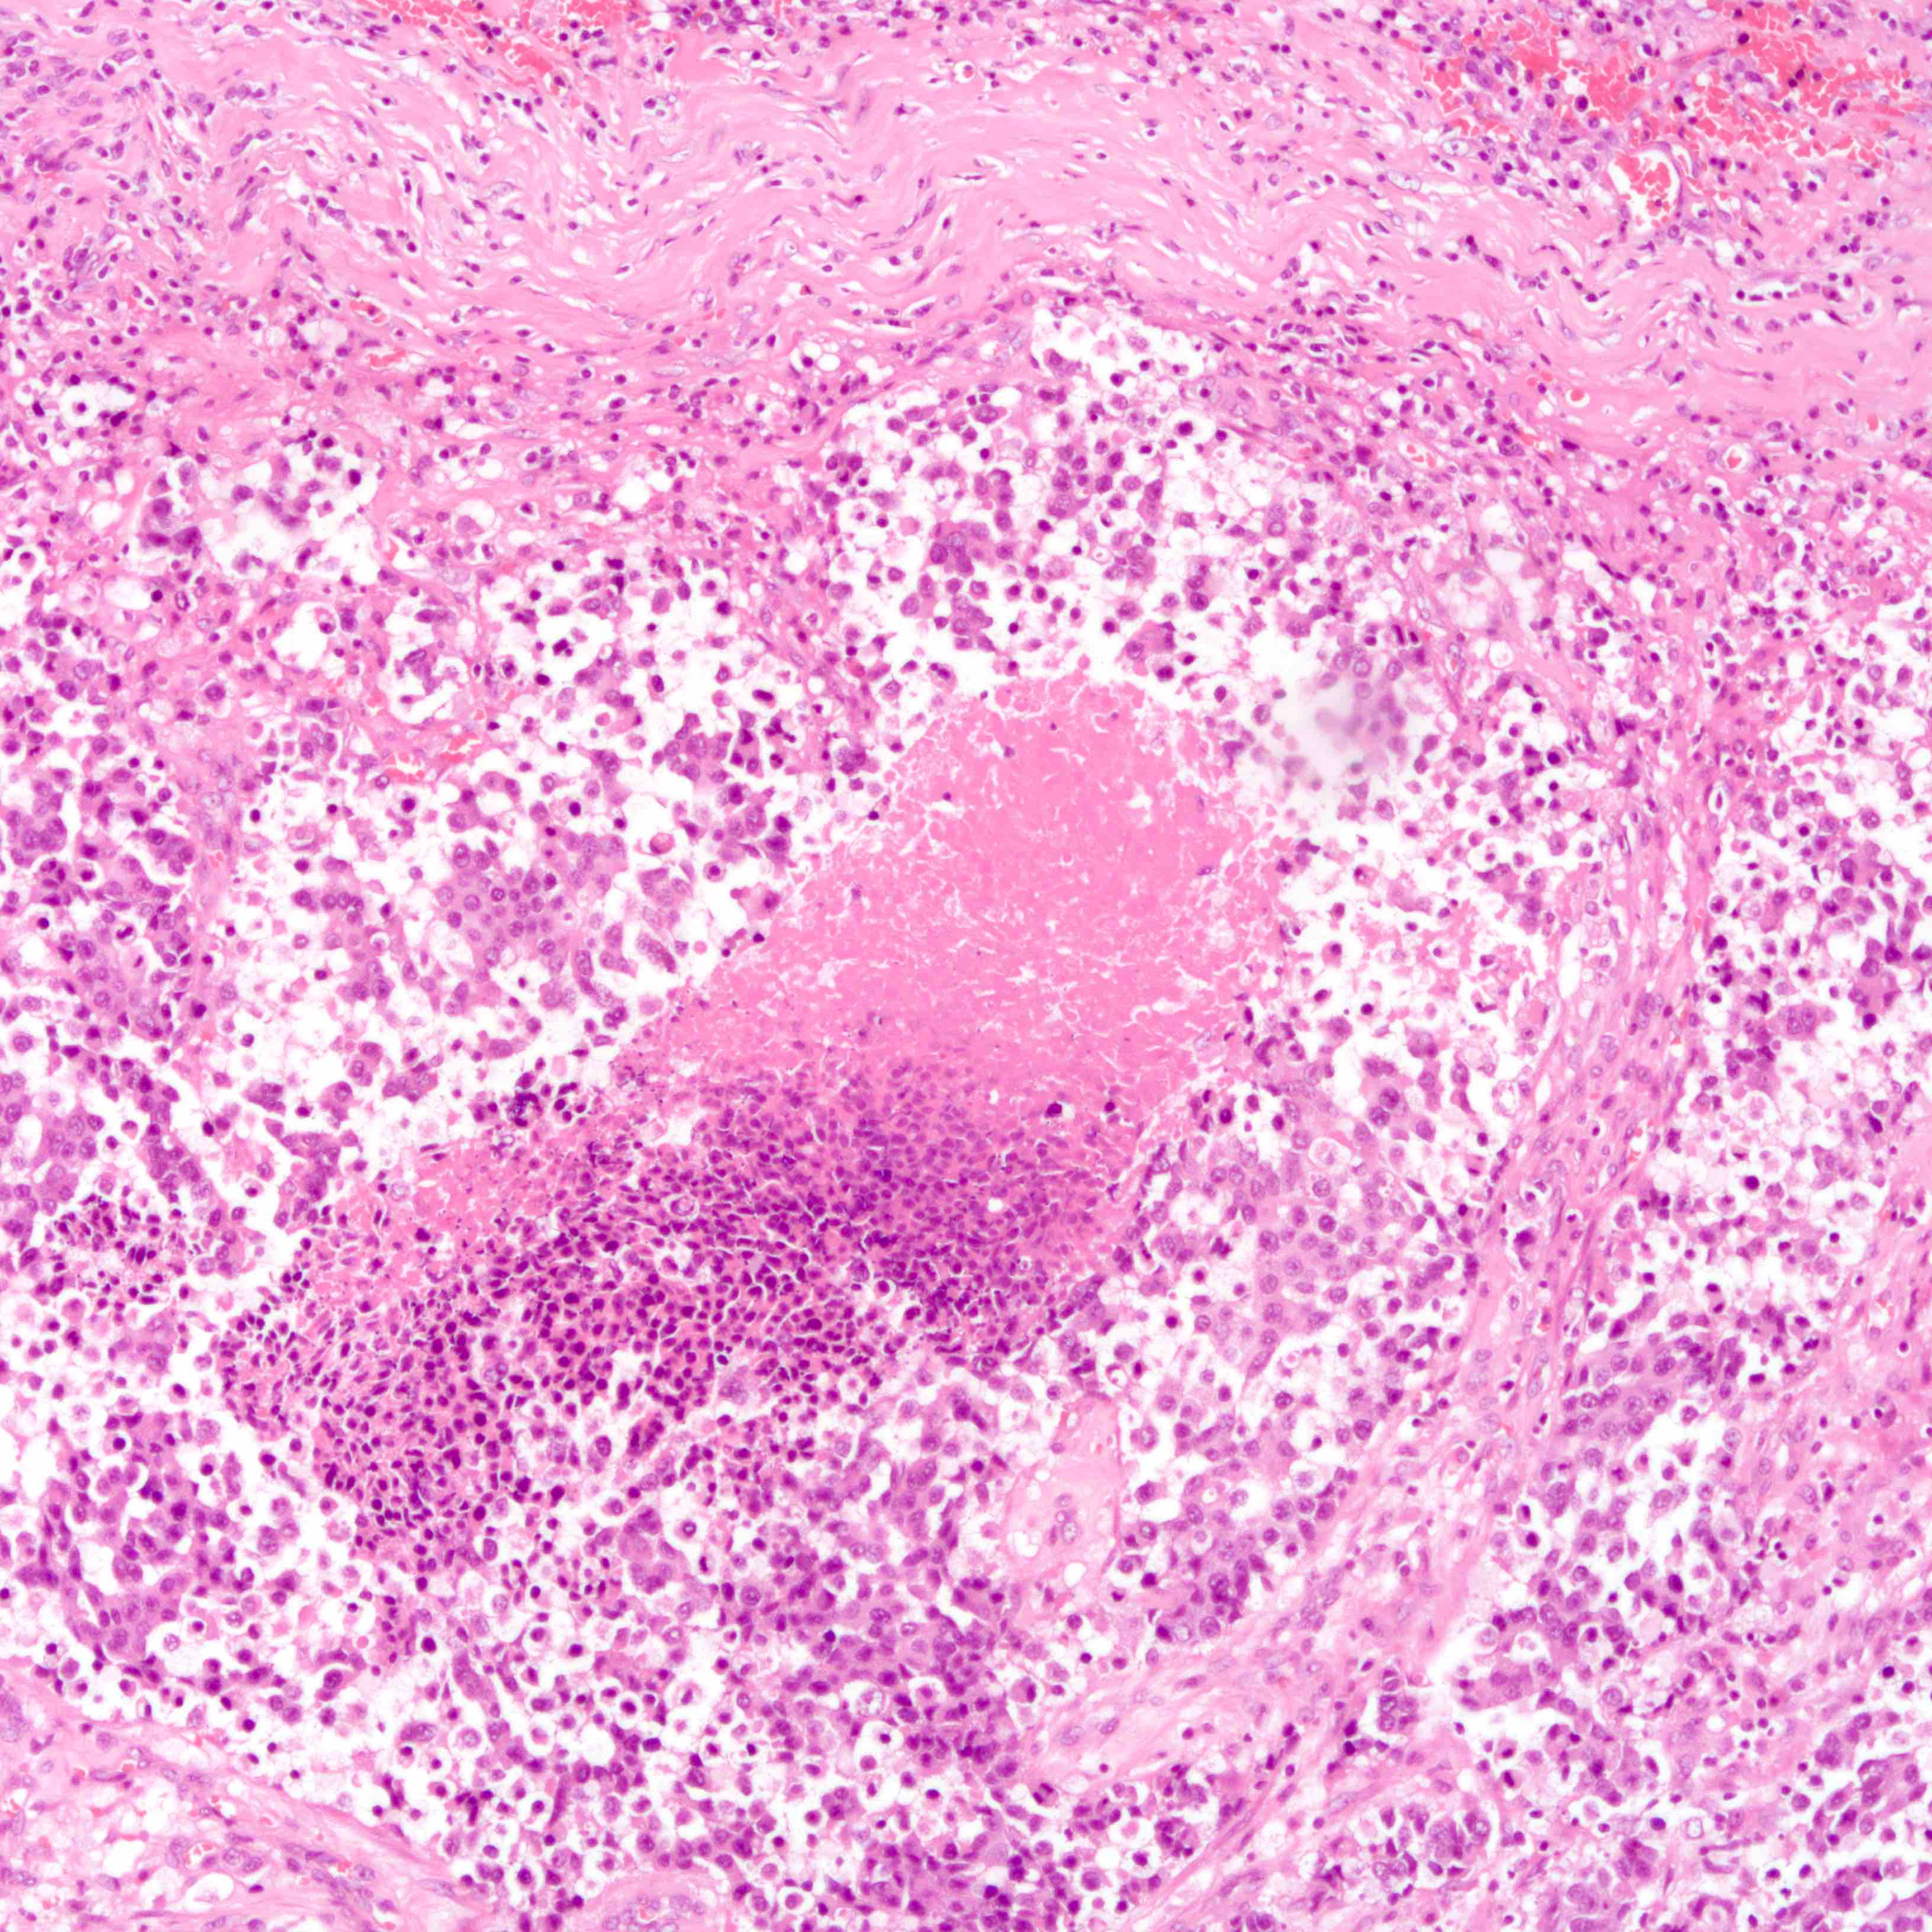

Microscopic (histologic) description

- Histologic evidence of tumor response includes fibrosis, hyalinization, lymphohistiocytic infiltration, hemosiderin laden macrophages, giant cell formation and vascular proliferation

- These histologic features are indicative of the tumor bed

- Patterns observed in partial response includes concentric tumor shrinkage, reduction in tumor cellularity and scattered multifocal tumor deposits (Mod Pathol 2015;28:1185)

- Tumor cells show degenerative changes including nuclear and cytoplasmic vacuolation, karyorrhexis, karyolysis and pyknosis (Int J Appl Basic Med Res 2012;2:111)

- Normal breast tissue shows ductal and lobular atrophy, atypia and hyalinization of vessel wall

- Lymph node

- Histological evidence of tumor response in the lymph node includes fibrosis, mucin pools, histiocytic infiltrates and lymphoid depletion

Microscopic (histologic) images

Contributed by Joshua J.X. Li, M.B.Ch.B., Gary M. Tse, M.B.B.S. and Emily S. Reisenbichler, M.D.